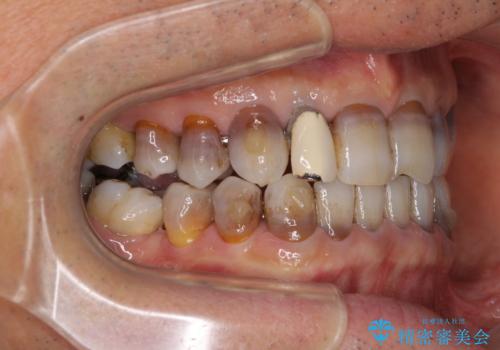

インビザラインは四六時中上下のマウスピースを介した咬合状態となるため、治療過程にて奥歯が接触しないという状態が続くことがあります。

奥歯の非接触は機能面において大きな障害であるため、この問題を解決しない限り矯正治療を終えることはできません。

インビザラインでの矯正治療が長期化してしまう要因の1つです。